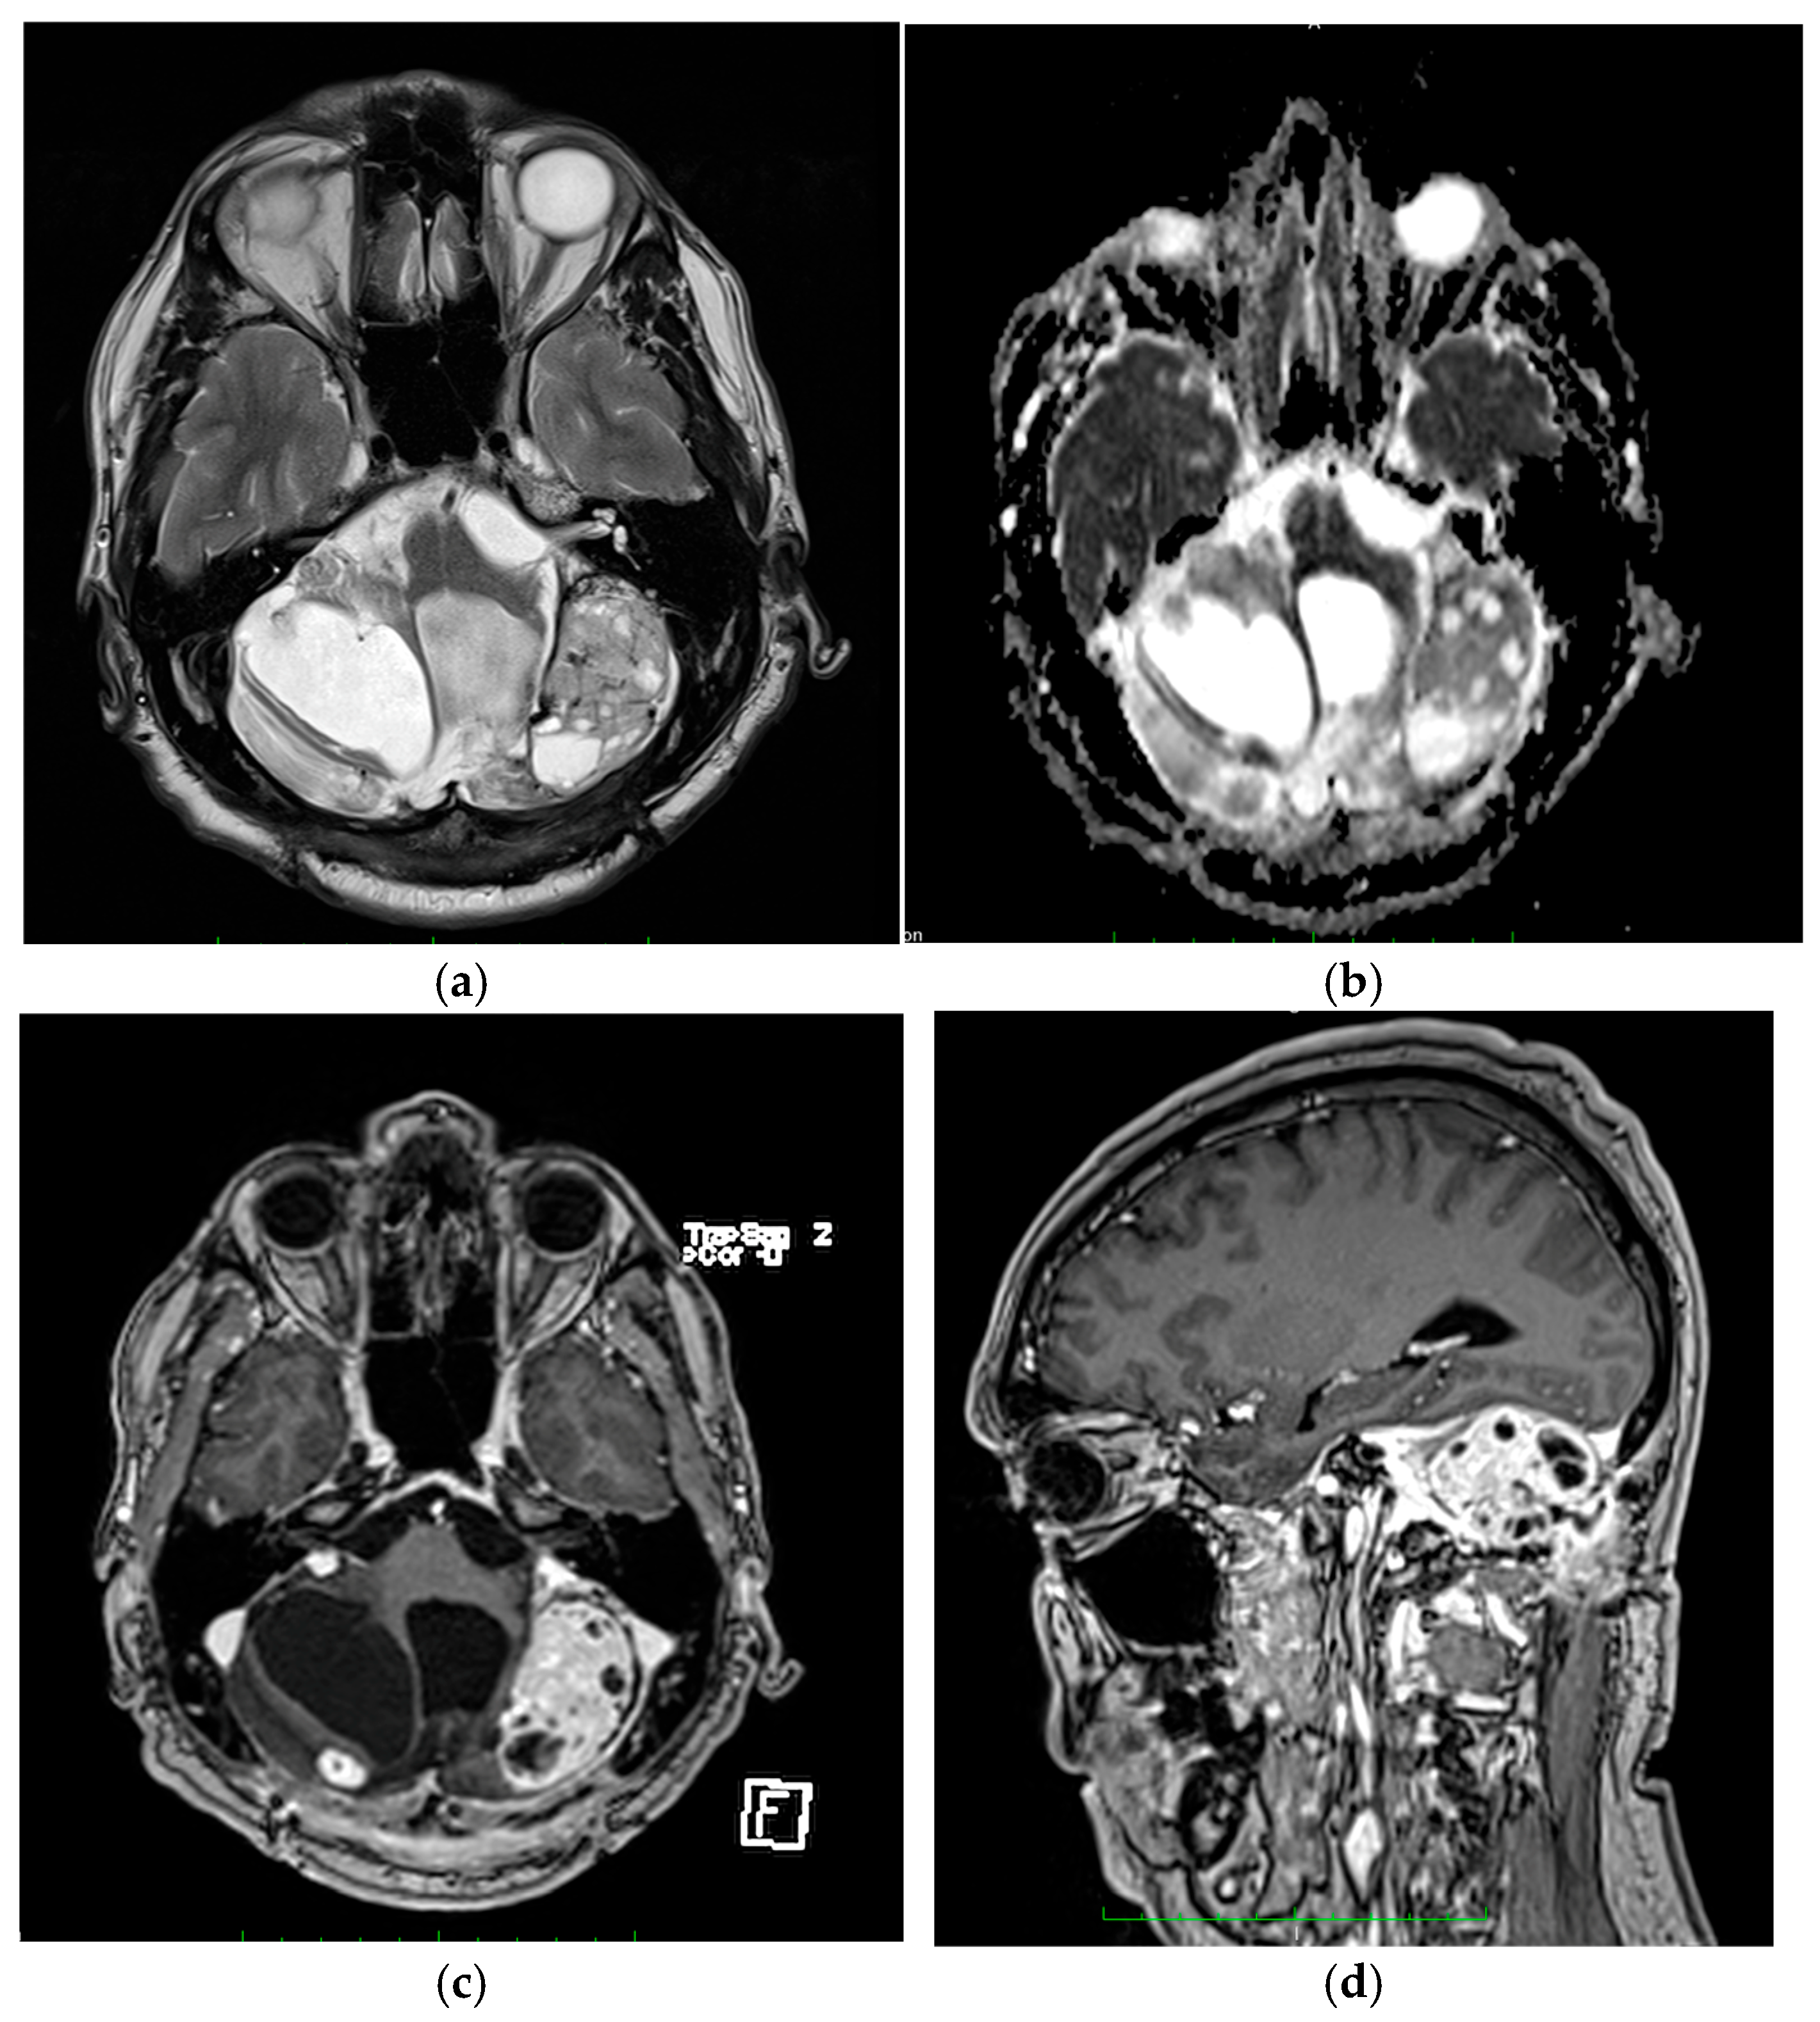

3.1.3. Patient Three